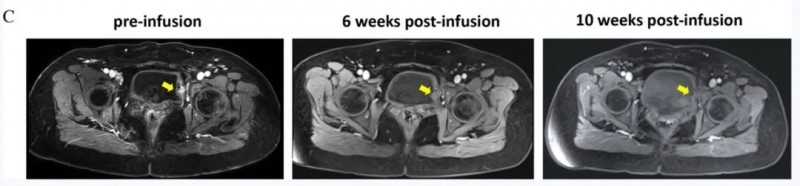

TIL细胞联合PD-1疗法,精准狙击复发性宫颈癌,10周完全缓解

全球知名期刊《BMJ Journals》曾报道一则振奋人心的案例(临床试验编号:NCT04766320):一名复发性宫颈癌患者经TIL细胞治疗后实现完全缓解(CR)。

该患者为52岁女性,2019年5月确诊IB3r期宫颈癌,随即接受根治性子宫切除术联合盆腔淋巴结清扫术。术后病理分期升级为IIIC1p期(盆腔淋巴结受累),后续完成4个周期紫杉醇脂质体联合奥沙利铂化疗。17个月后,核磁共振成像(MRI)提示膀胱复发,患者接受部分膀胱切除术,术后继续辅助化疗,同时留存肿瘤切除物用于制备TIL细胞。入组本研究后,患者依次接受环磷酰胺静脉输注、TIL细胞回输及PD-1抗体治疗。

疗效数据十分亮眼:TIL细胞输注6周(42天)后,T1WI影像显示病灶显著缩小(黄色箭头标注),首次临床评估提示患者无发热、体重减轻等异常症状,体格检查未触及浅表淋巴结肿大;依据RECISTv1.1标准,输注10周后正式确认患者达到完全缓解(CR,详见下图)。

▲图源“BMJ journals”,版权归原作者所有,如无意中侵犯了知识产权,请联系我们删除